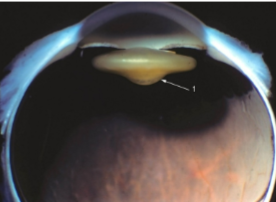

microphakia